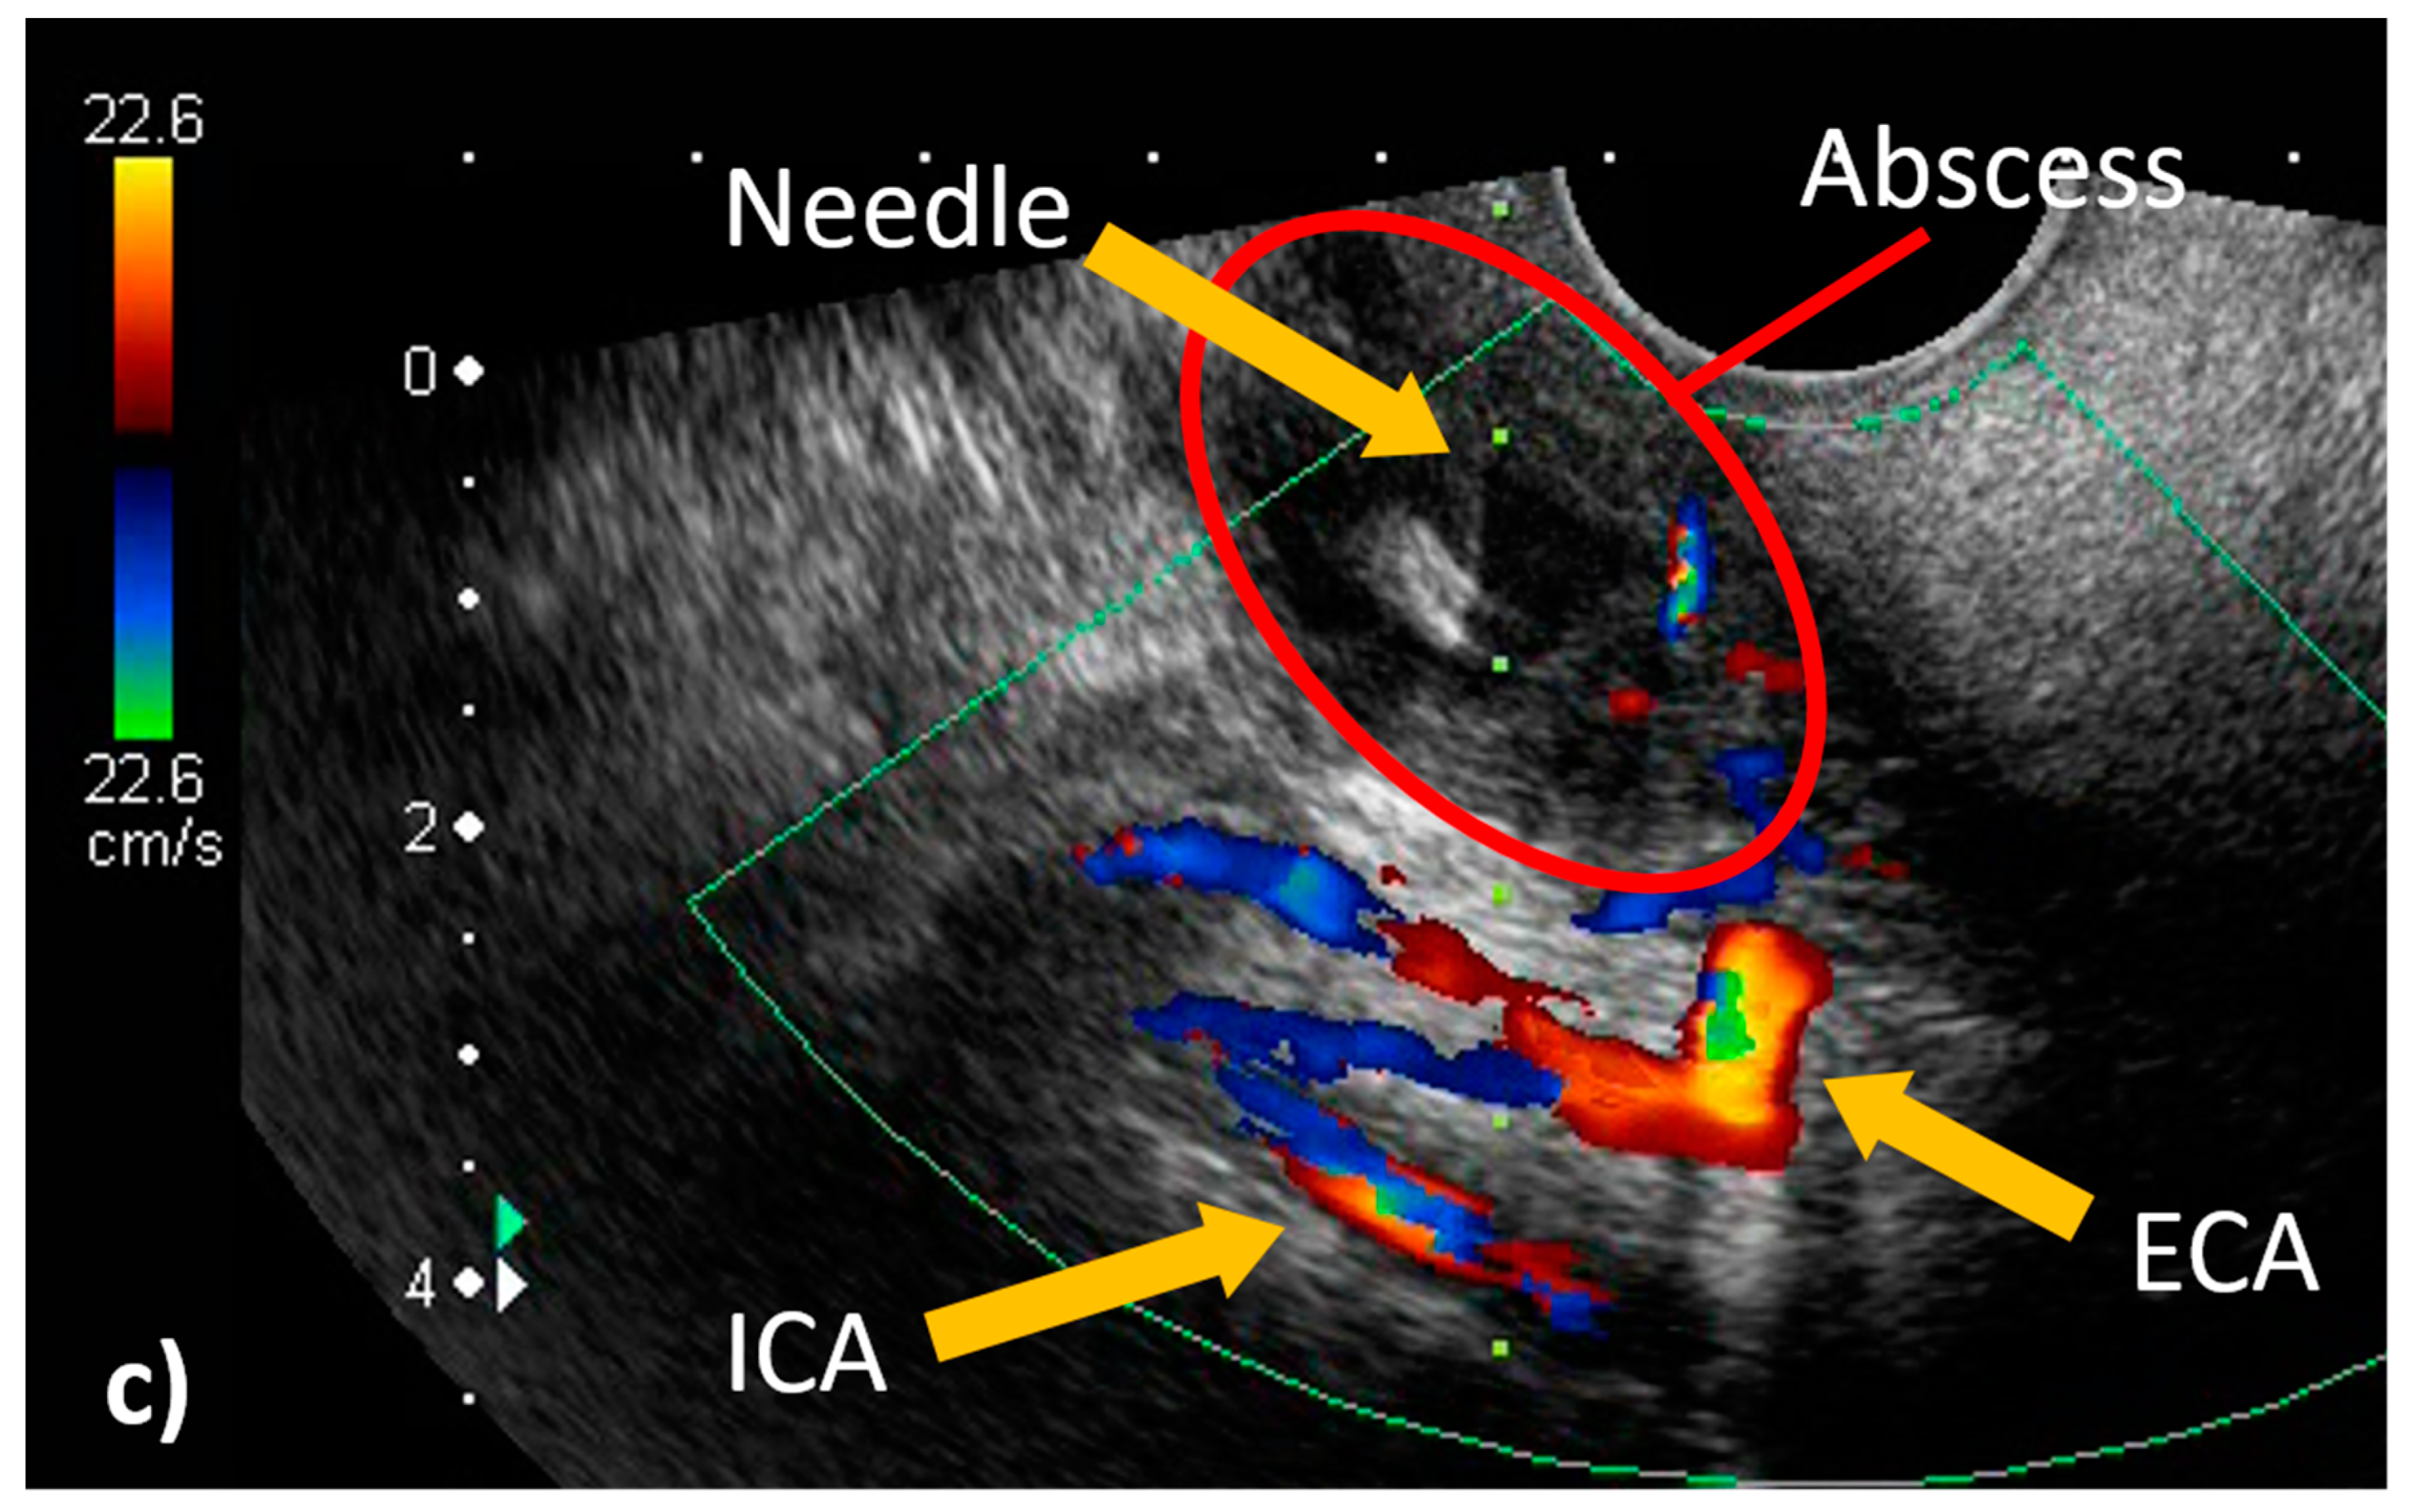

Figure 4.

Transoral pharyngeal ultrasonography (TOPU). (a) TOPU with B-mode. (b) TOPU with color Doppler. The left side of the image is the head side, and the right side is the foot side. TOPU shows the internal carotid artery (ICA) under the abscess at a depth of 30–40 mm and the external carotid artery (ECA) just under the abscess at a depth of 20–30 mm. The branches of the ECA surround the head side of the abscess. The tip of the needle is inserted at the center of the abscess in the hypoechoic space. The vertical green dotted line indicates the direction in which the needle advances; this guiding line system is incorporated in the ultrasound machine (Aplio500). (c) Schematic image. The periphery of the abscess is indicated by the red circle. It is easy to differentiate between the ICA and ECA because the branch arteries are visualized along with the ECA.